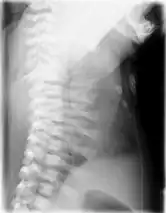

CXR of a newborn with asphyxiating thoracic dysplasia. Note the short ribs.

Lateral CXR of the same person above